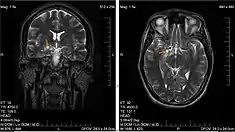

| Glioma | |

| Glioma in the left parietal lobe (brain CT scan), WHO grade 2 | |